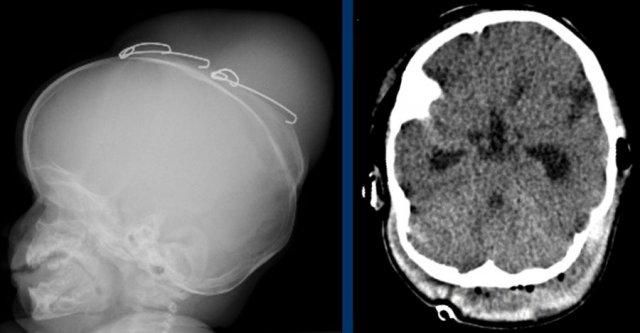

Tăng áp lực nội sọ.

TRÁI: Các vết ấn lõm trên phim X-quang sọ có độ nhạy thấp, đặc biệt ở trẻ nhỏ, nhưng khi xuất hiện, chúng rất gợi ý tình trạng tăng áp lực nội sọ.

PHẢI: Não úng thủy với dòng chảy tâm trương đảo ngược, biểu hiện của tăng áp lực nội sọ.